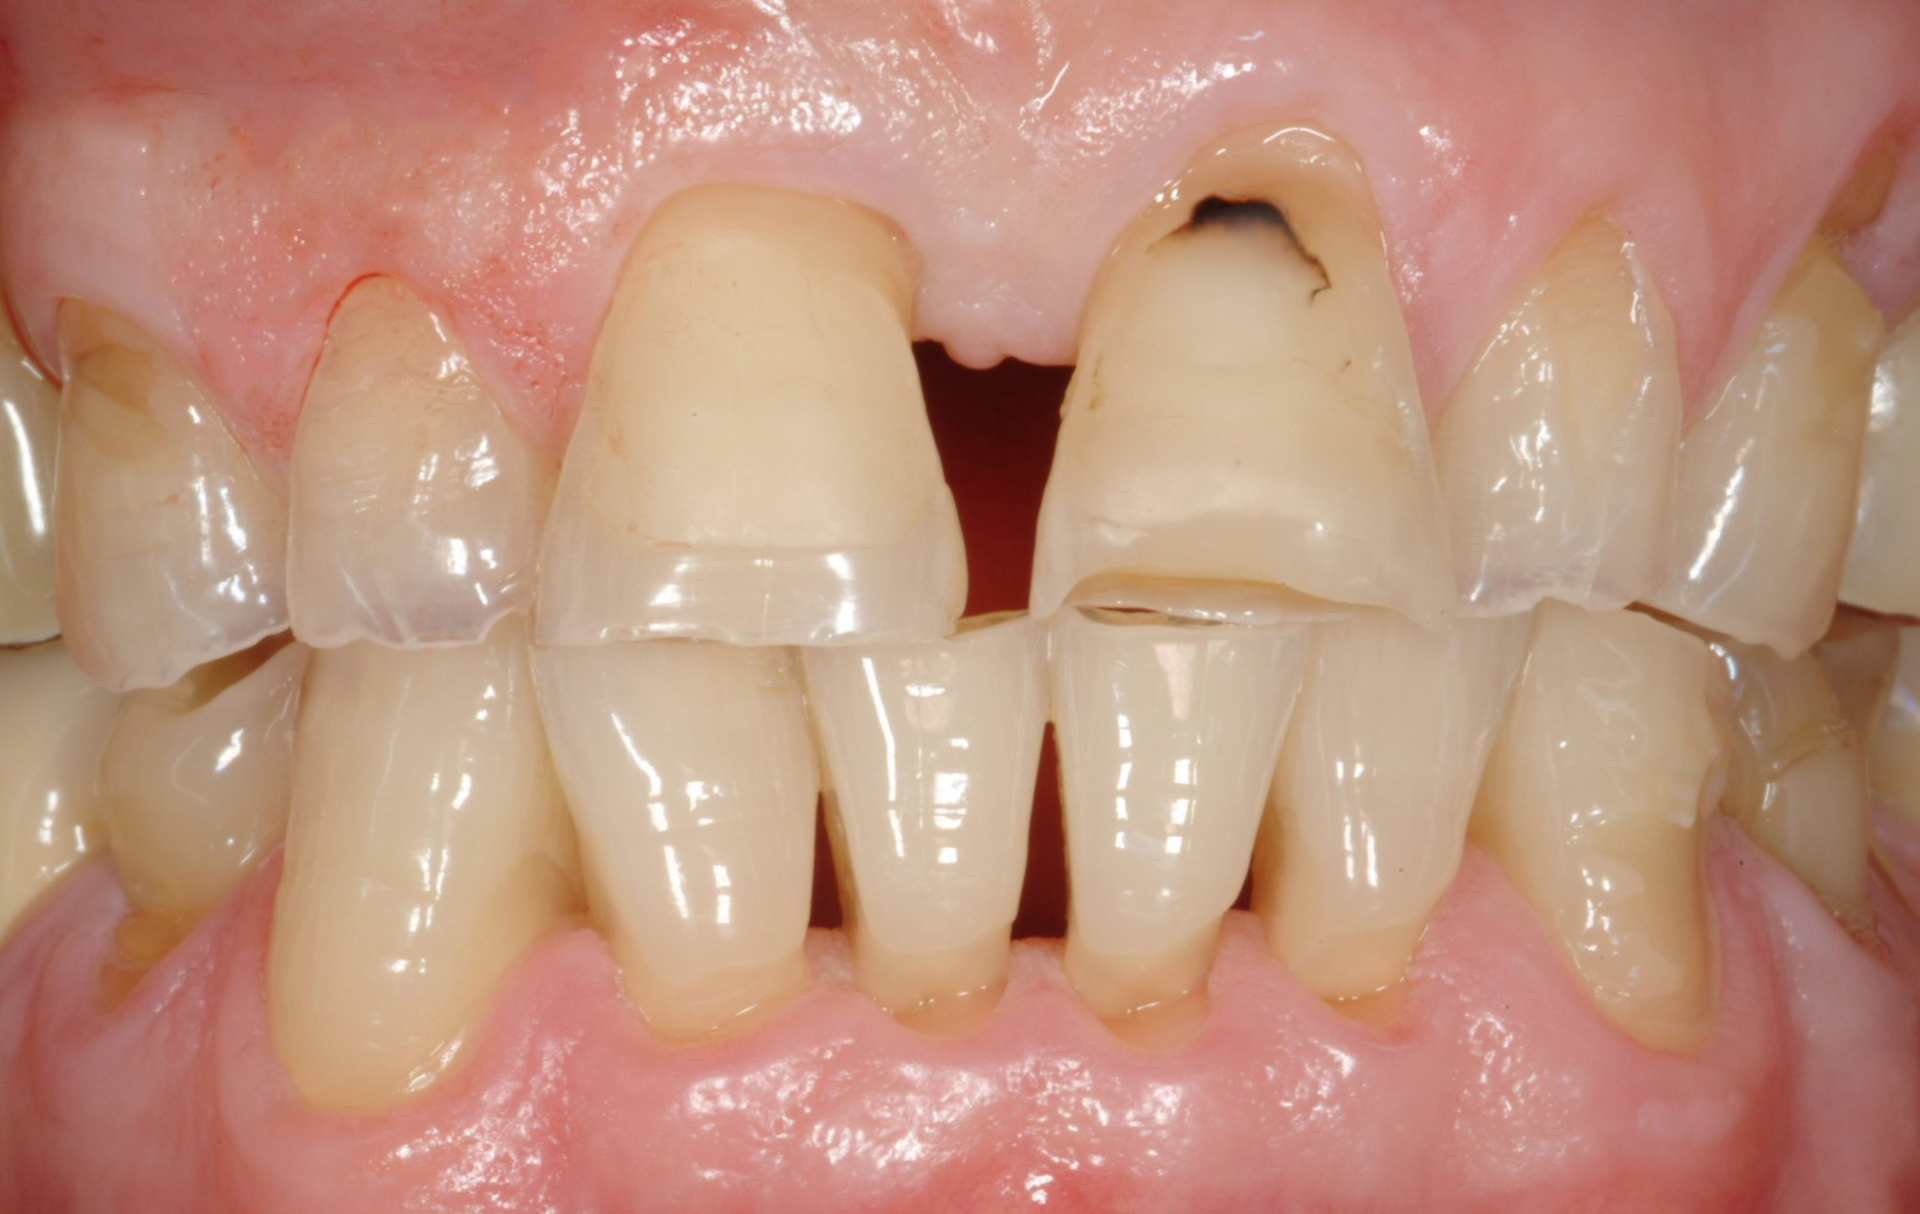

Faccette in ceramica

Le faccette in ceramica sono sottili lamine personalizzate che vengono applicate sulla superficie anteriore dei denti per migliorare l'estetica del sorriso. Questi dispositivi sono ideali per correggere imperfezioni come macchie, scheggiature, denti disallineati o spazi eccessivi. Le faccette in ceramica offrono un risultato naturale e duraturo, grazie alla loro resistenza e alla capacità di imitare l'aspetto dei denti naturali. Lo studio garantisce un'applicazione precisa e personalizzata, adattando le faccette alle esigenze estetiche e funzionali di ogni paziente.